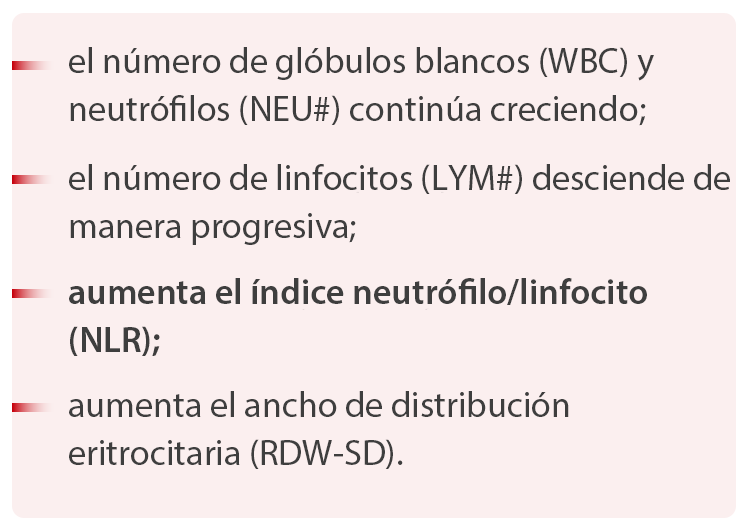

A.?De la comparaciÃġn de los hemogramas de casos moderados y graves se puede concluir que, a medida que el paciente va empeorando:

Este artÃculo estudiÃġ los cambios de los resultados de los hemogramas de 45 pacientes con COVID-19 en diferentes etapas. La tendencia del LYM# concuerda con lo descrito en la 6.? ediciÃġn del Provisional Criteria for Diagnosis and Treatment of COVID-19. AdemÃḂs, el equipo de investigaciÃġn dirigido por el profesor Nanshan Zhong, miembro de la Academia de IngenierÃa China y renombrado experto en enfermedades respiratorias, ha publicado un estudio sobre 1099 casos de COVID-19 que muestra que el descenso proporcional de linfocitos alcanzÃġ el 82,1 %. [3]

Con respecto al parÃḂmetro NLR, el resultado del estudio se corresponde con la tendencia descrita en el artÃculo, Neutrophil-to-Lymphocyte Ratio Predicts Severe Illness Patients with 2019 Novel Coronavirus in the Early Stage, una preimpresiÃġn publicada por el Hospital Ditan de PekÃn en la plataforma medRxiv. [4] El artÃculo se?ala que el NLR se puede usar como parÃḂmetro para alertar de manera temprana un posible caso de deterioro agudo del estado de salud en pacientes con COVID-19.